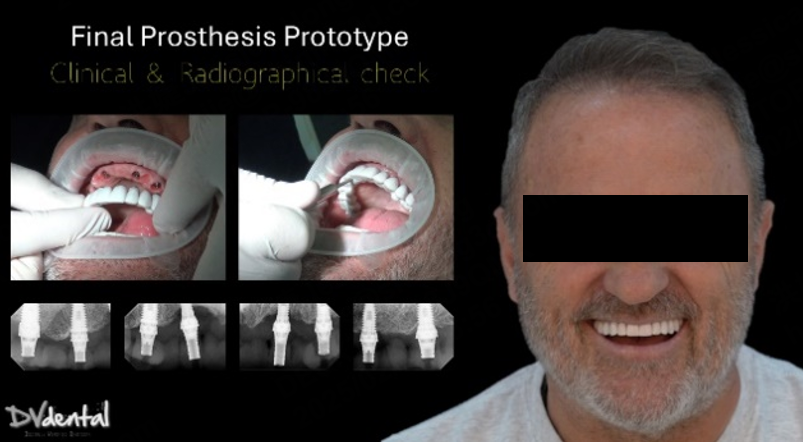

4. Try-in

Before the permanent prosthesis, a prototype of it has been created for intraoral try-in. This is a good way to check the fit of our prosthesis clinically and radiographically while assessing the aesthetics simultaneously. After the successful try-in, the manufacturing of the permanent prosthesis (Zirconia full contour on Ti bases) will proceed. Finally, periapical X-rays show that the permanent prosthesis fits excellently, and the aesthetic outcome was exactly as planned, the patient is really happy about the result.